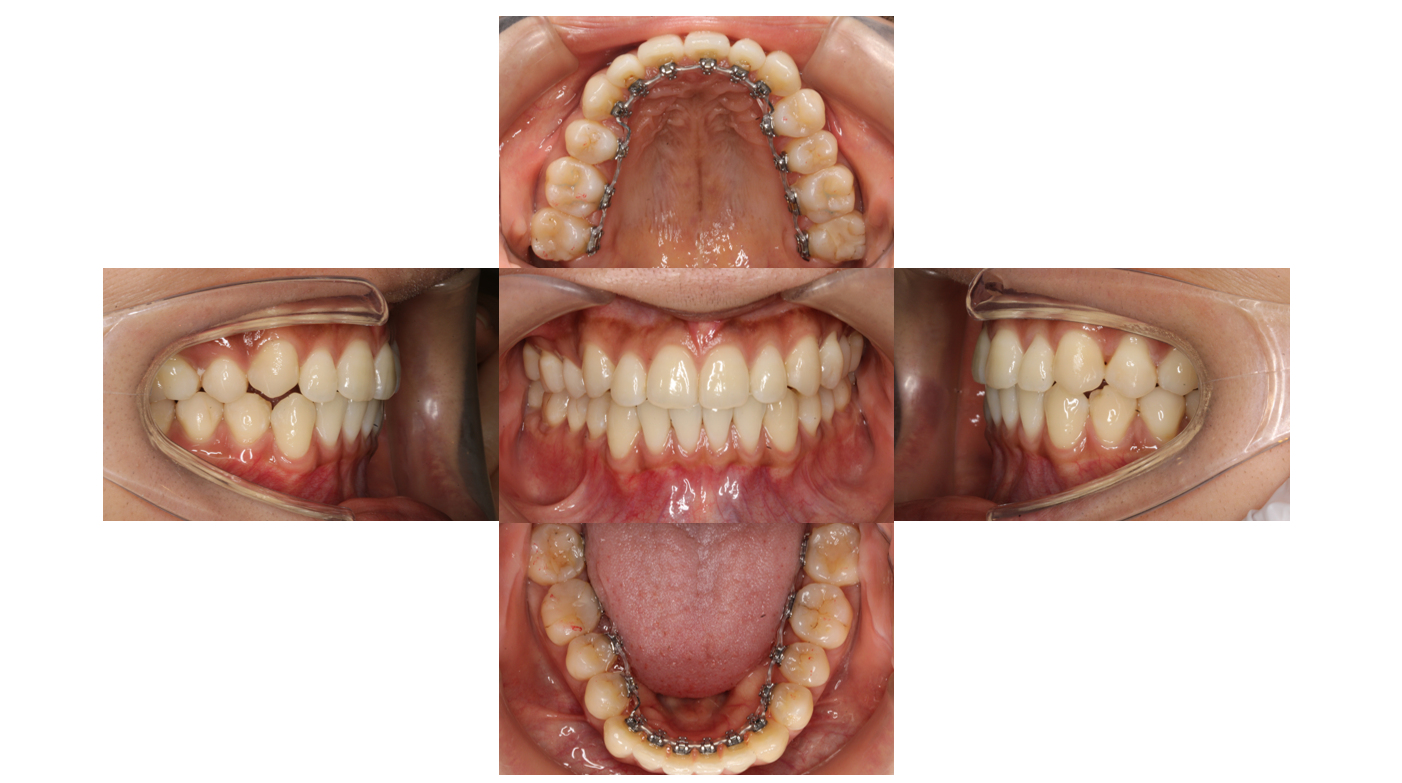

かみ合わせを治したい(治療期間:1年6か月経過 治療回数:19回)

After

| 主訴 | 【主訴】かみ合わせが合わない 【診断・症状】不正咬合 |

| 治療期間 | 1年6か月(19回) |

| 抜歯 | 有(上4) |

| 矯正の装置 | 裏側矯正(舌側矯正) |